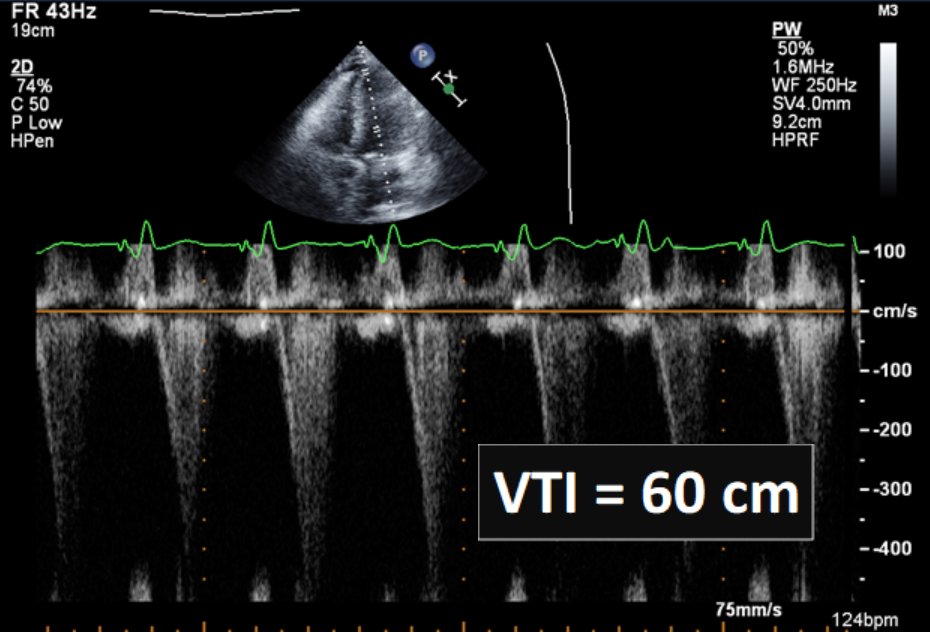

#CriticalCareQuiz A 75-year-old man has urosepsis; no prior history. BP 95/52, HR 124, lactate 6. TTE shows EF 75%. VTI is 60 cm from pulsed wave Doppler. LVOT diameter is 2 cm, which yields CO 23.4 L/min. MV CW Doppler is also shown. Why is CO so high? #SCCMSoMe